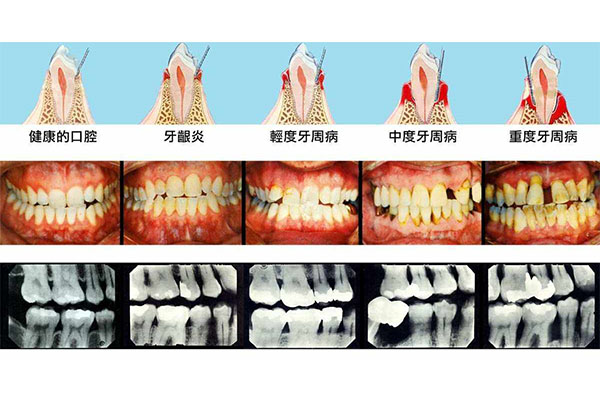

首先,牙周病。如果牙齿四周的组织发生病变,牙石堆积在牙齿上,容易导致牙龈毛细血管扩张充血,牙龈水肿疼痛。一旦机体在刷牙不当或者咀嚼比较硬的食物时,就会出现出血症状。

第三,牙结石刺激。如果牙颈部有很多细菌,会刺激到牙龈,使牙龈出现红肿、发炎、疼痛,严重时会出血。第四,全身疾病。如果患者患有肝硬化、血友病、老年高血压、血液病等,容易在刷牙时出血。建议根据出血严重程度到医院进一步检查,明确病因,对症治疗。